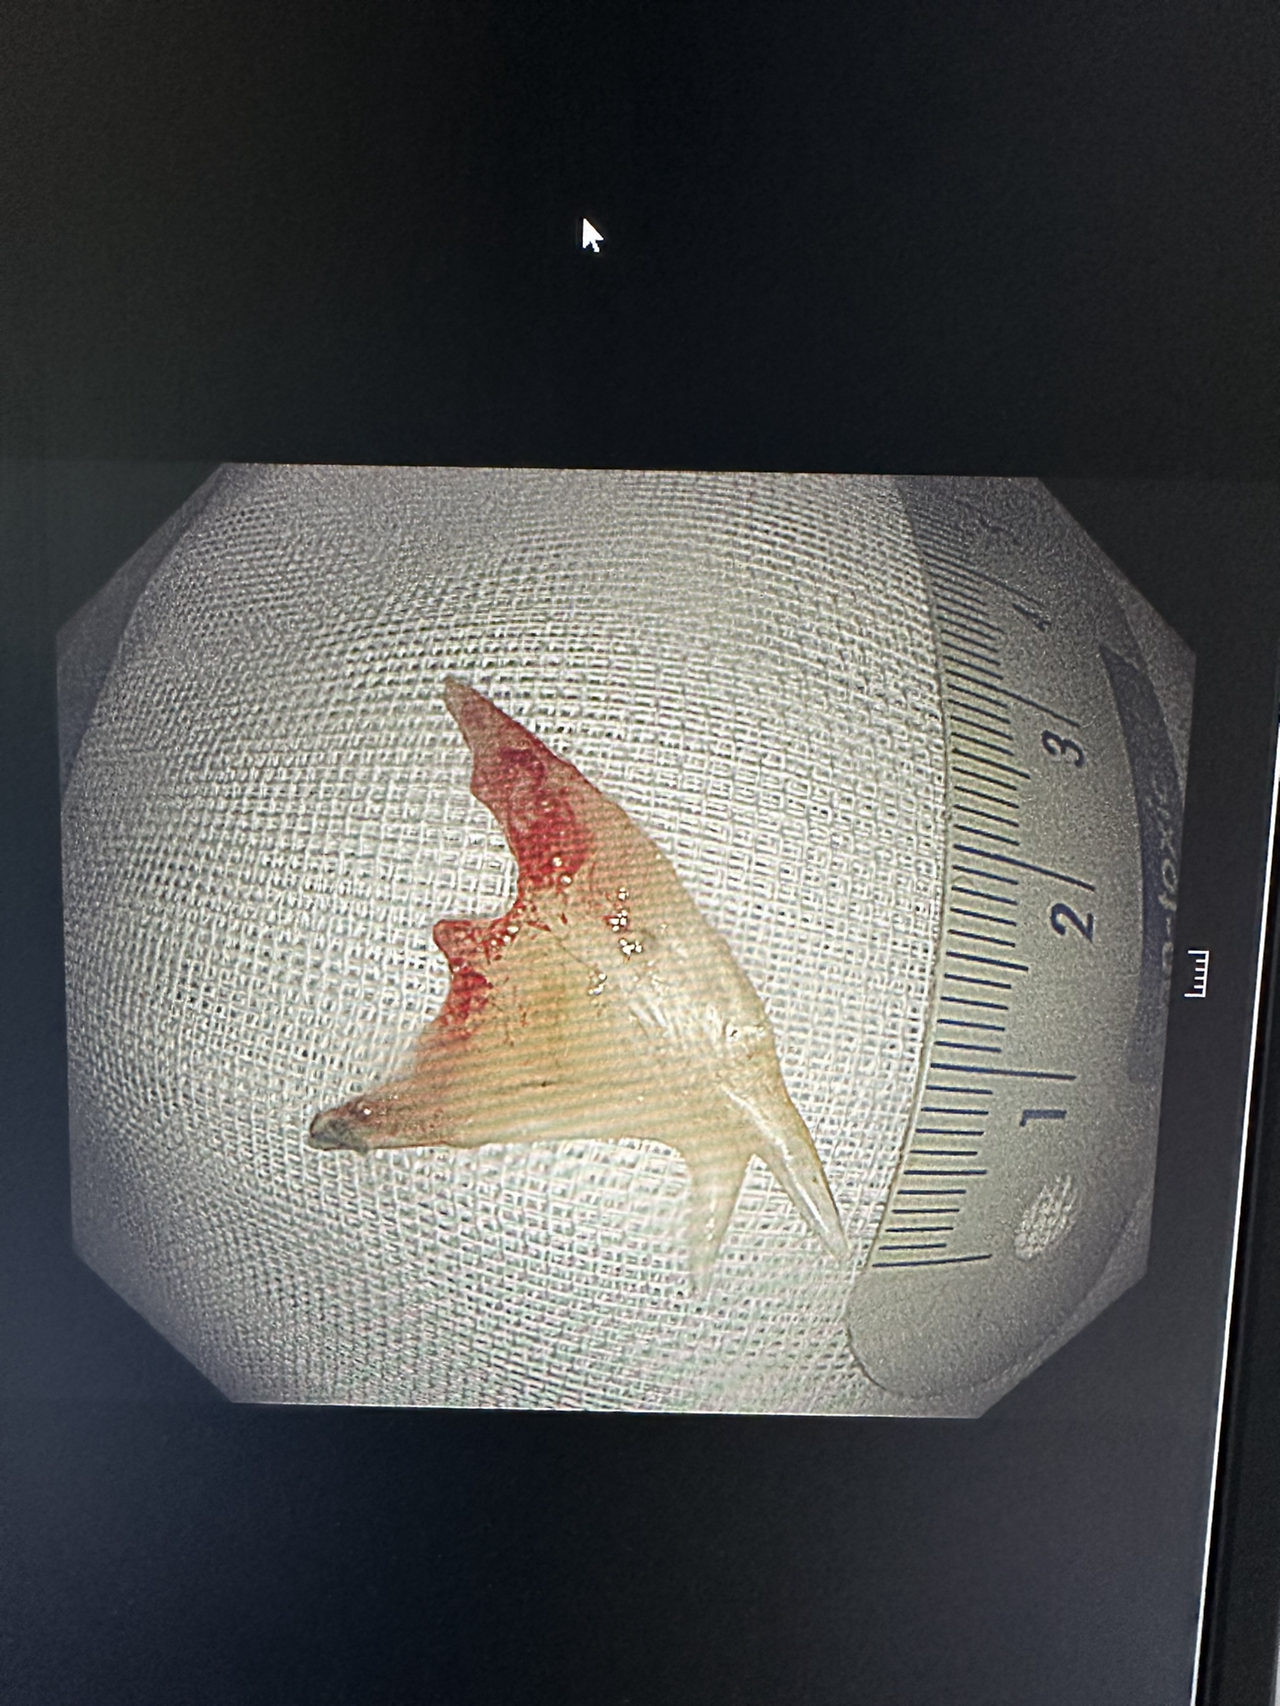

몇 개월 동안 뺐던 생선 가시들이다. 얼핏 보면 커 보이지 않지만 pyriforn sinus(이상와)의 크기보다 큰 이물들은 나오면서도 상처가 생길 수 있고 식도에도 상처를 입힌다. 몇 년 전, 생선 가시가 식도에 박혀있는 환자가 종합병원에서 내시경을 하고 응급실로 왔었다. CT상엔 동맥에 1/3이 침범해 있었고 가시가 박혀 있는 주변부는 농이 나오고 있었다. 다음날 수술실에서 흉부외과와 조인해서 내시경을 했다. 우리가 내시경으로 가이드를 하고 가시를 제거하면 출혈을 잡지 못할 것이기에 개흉수술을 바로 진행할 예정이었다. 다행히 출혈은 심하지 않았고 내시경적으로 해결할 수 있었지만 그 아찔함이란. 그만큼 생선가시를 삼키면 위험하다. 김치나 밥을 삼켜 빼는 것보단 내시경적으로 제거하는 것이 바람직하다.